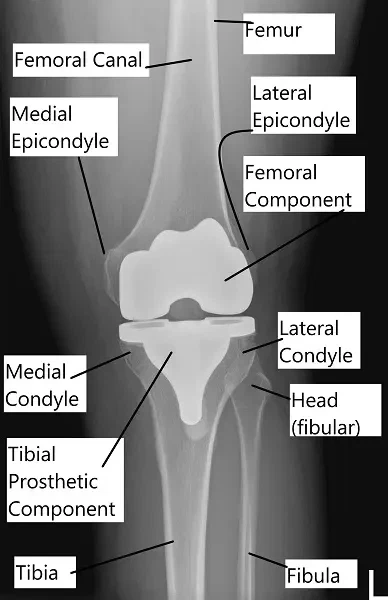

Las imágenes anteriores muestran los componentes protésicos de la prótesis de rodilla por delante y por detrás. El componente femoral (estabilizado posterior) tiene un mecanismo de leva que permite la traslación posterior del fémur sobre el poste tibial de la superficie de apoyo.

El retroceso femoral ayuda a conseguir una flexión más profunda, que en una rodilla normal realizan los ligamentos de la rodilla. El inserto de polietileno está hecho de polietileno altamente reticulado, que es resistente al desgaste. La quilla del componente tibial se fija en la parte superior de la tibia mediante cemento óseo.